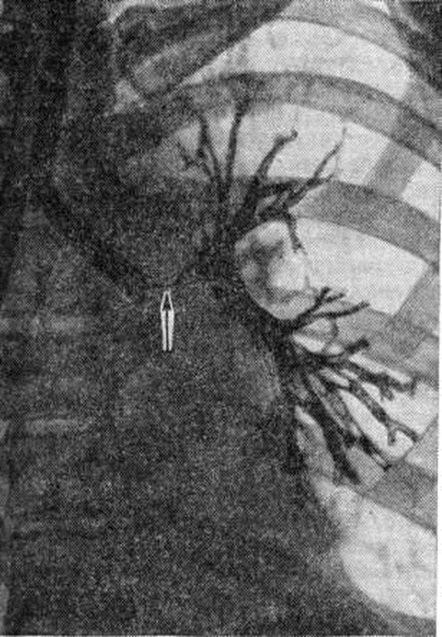

Фотографии и информация о бронхоскопии при туберкулезе